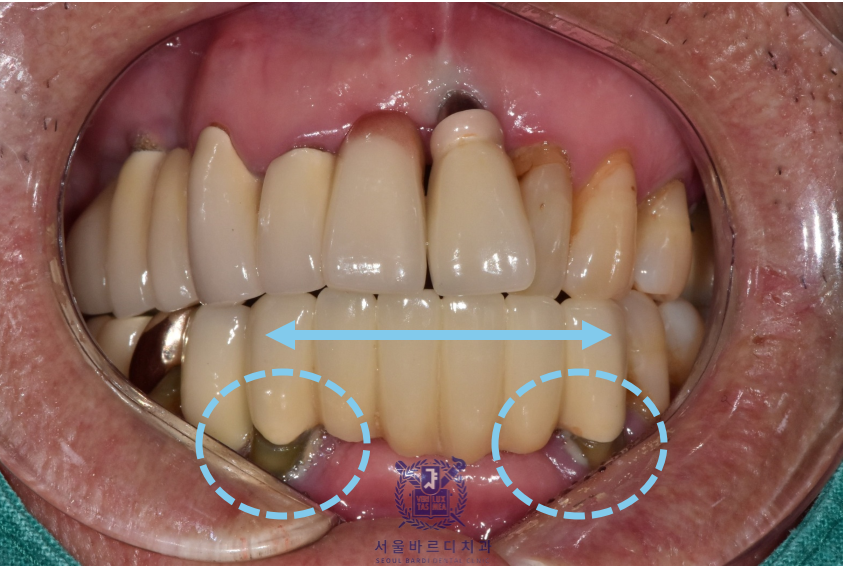

앞으로 새로 할 보철은 깨끗한 색이였으면 한다고 하셔서

앞니는 조금 밝은 색으로 진행하게 되었습니다.

아래 컬러에 맞춰 기존에 있는 보철들도 추후 차례대로 교체하기로하셨습니다.

앞니는 기능적이면도 있지만 심미적인 측면이 매우 중요하기 때문에

최대한 환자분에게 적합한 형태로

환자분의 의견을 적극 반영하여 제작하고 있습니다.

이전의 브릿지 보철은 공간을 꽉 채우는 느낌으로 제작되어

이가 너무 길어보이는 느낌이 있어

이번에는 볼륨을 통해 치아가 길어보이지 않게 제작했습니다.

실제로 치아가 보이는 부분은 이 앞의 보철과는 다르게

짧게 표현되어 환자분이 아주 만족스러워하셨습니다.

더불어 뭉툭하고 긴 치아표면으로 인해 양치가 어려웠지만

이번 디자인은 치아가 볼륨을 통해 나눠져 있어

양치하시기도 훨씬 수월하시다고 합니다.